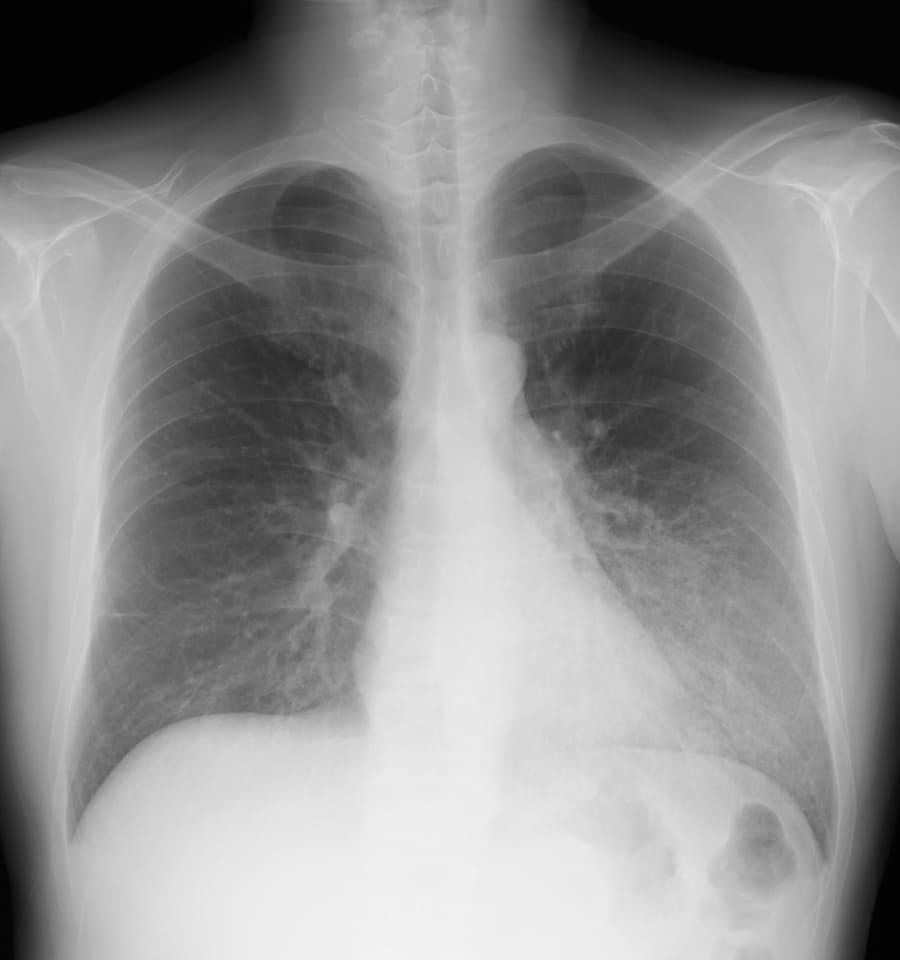

- Q3 呼吸困難を訴える40代男性(事務職)

呼吸困難を訴える40代男性(事務職)

DATA 1| X 線検査結果

画像にマウスオン(またはタップ)すると虫眼鏡で拡大できます